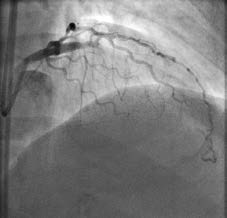

Coronary angiogram immediately following successful stenting of the occlusion using the reverse controlled antegrade and retrograde tracking (CART) technique. Allina Health Minneapolis Heart Institute was the first center in the Upper Midwest to use this novel approach to open chronic total occlusions and it now trains interventional cardiologists at other regional centers in using the technique.